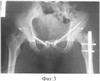

Фиг.3. Рентгенограмма таза после операции.

Больной В., 25 лет, история болезни 3710, госпитализирован на 1-е сутки после получения травмы с диагнозом: Сочетанная травма. Сотрясение головного мозга. Перелом лонной и седалищной костей таза слева. Перелом седалищной кости таза справа. Разрыв лонного сочленения. Перелом дна и задней стенки левой вертлужной впадины. Поперечный перелом средней трети левой бедренной кости. Внутрисуставной оскольчатый перелом медиального мыщелка левой большеберцовой кости. Продольный оскольчатый перелом левой лучевой кости (фиг.2). На четвертые сутки больному произведена операция: металлодез лонного сочленения в надлобковой области. Произведен разрез до 5 см, выделено место разрыва, затем при помощи сверла сформировались отверстия в области бугорков лонных костей, идущие косо вниз и кнутри под углом до 20°. После охлаждения скобы с металлопамятью формы и сведения лонных костей до полного контакта внедряют бранши скобы в заранее приготовленные отверстия. При температуре тела скоба возвращается в изначальную форму, тем самым удерживая лонное сочленение (фиг.3). Остеосинтез передней колонны вертлужной впадины слева спицей с нарезкой, остеосинтез лонной кости блокируемым винтом, интрамедуллярный остеосинтез левой бедренной кости. Послеоперационный период протекал без особенностей. Больной активизирован на 1-е сутки в пределах кровати, а на 2-е сутки поставлен на костыли. Функция восстановлена полностью. Больной осмотрен через один год после оперативного вмешательства (фиг.4). Жалоб нет, укорочений нижних конечностей нет, ходит без средств дополнительной опоры, полный безболезненный объем движений в тазобедренных суставах, нарушений со стороны сексуальной функции не отмечено. На рентгенограммах – взаимоотношения суставных поверхностей в лонном сочленении хорошие, отмечается консолидация переломов.